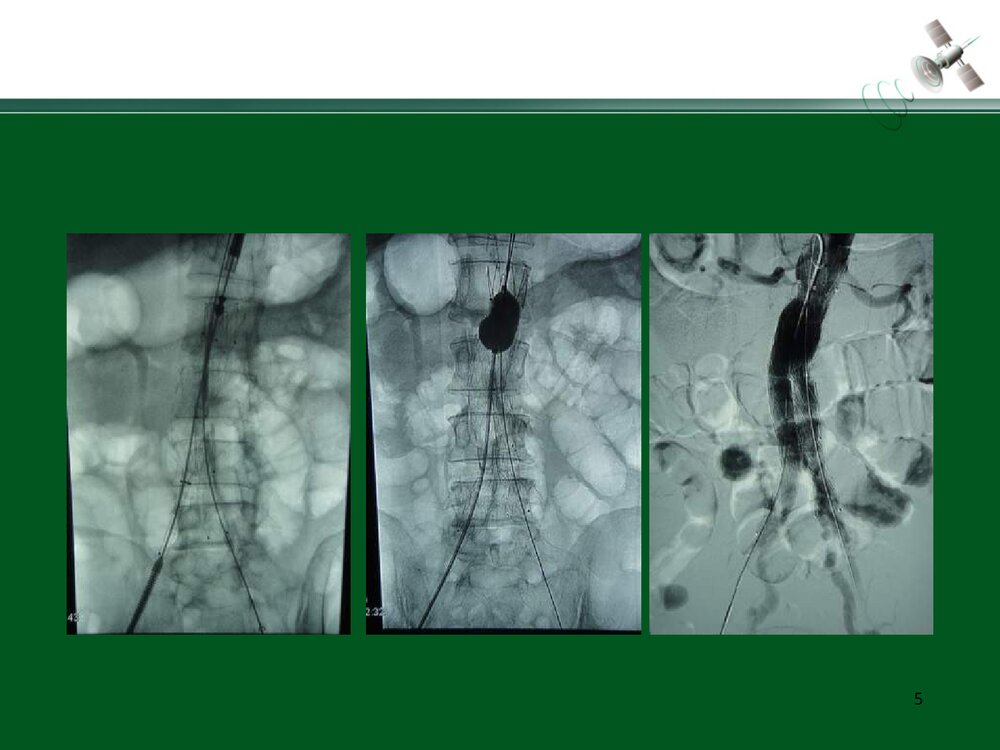

复杂腹主动脉瘤的腔内治疗常光其王深明教育部国家重点学科卫计委国家临床重点专科中山大学附属第一医院血管外科中山大学血管外科研究中心1复杂瘤颈AAA的腔内治疗复杂瘤颈指下列情况1.瘤颈长度小于15mm;2.瘤颈角度大于60度;3.瘤颈直径过大或过小(小于18mm或大于32mm)例1:短瘤颈AAA的EVAR3456例2:短瘤颈伴入路血管狭窄AAA的EVAR7891011例3:瘤颈狭窄且成角大于60度AAA的EVAR12131415161718192021例4:瘤颈成角大于60度AAA的EVAR2223242526例5:瘤颈成角伴腹主动脉分叉狭窄AAA的EVAR272829303132复杂入路AAA的腔内治疗复杂入路是指下列情况:(1)髂动脉弯曲成角超过90°;(2)双侧髂股动脉广泛钙化伴严重狭窄,直径小于7mm;(3)双侧髂股动脉闭塞例6:入路血管严重狭窄AAA的EVAR34353637383940例7:入路血管严重...